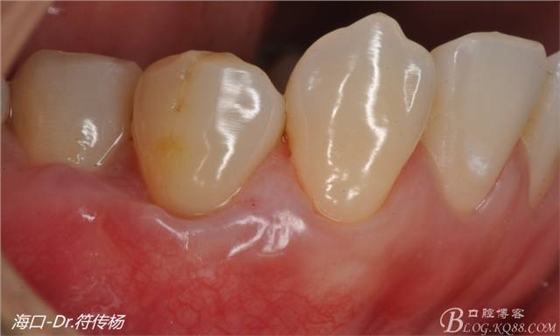

術(shù)后兩月